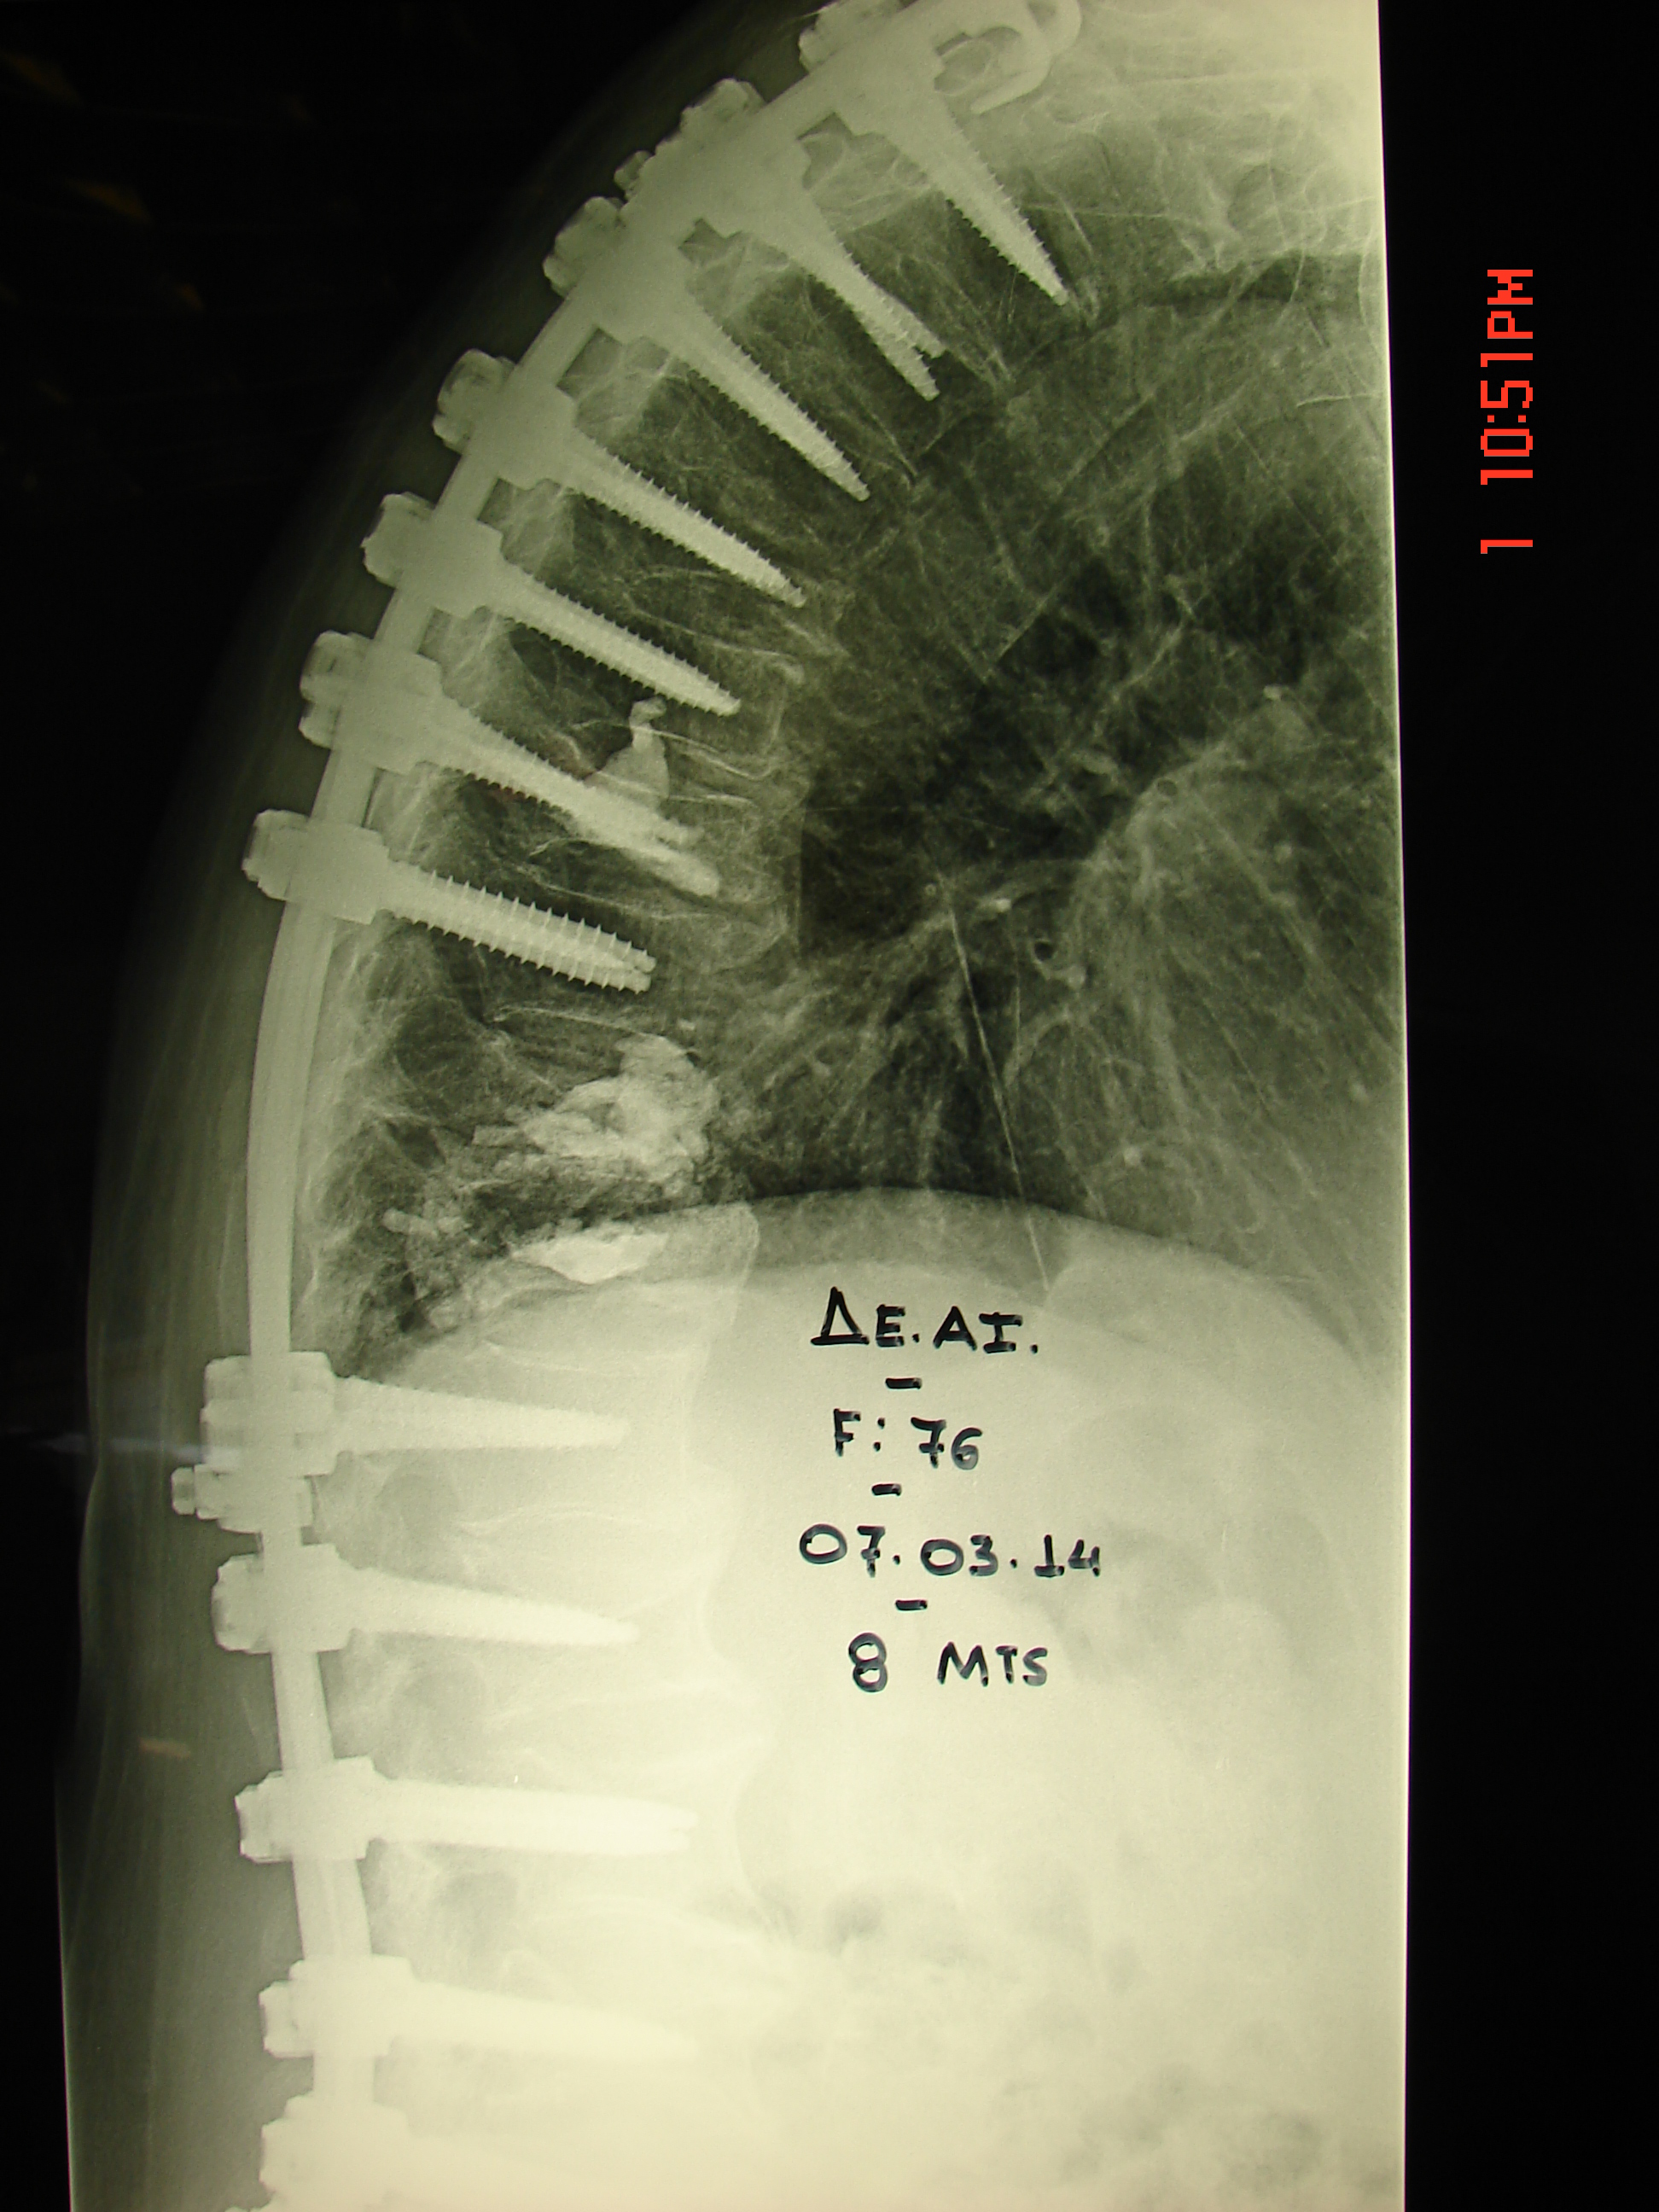

Εικόνα 6: α, β,γ, δ

Μετεγχειρητικές ακτινογραφίες, οκτώ μήνες μετά την επέμβαση